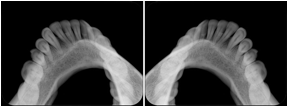

2 Occlusal Vertical Maxilla A Dental Image Layout

DL-C001A

Reference: DL-C001-U1L0

Reference: DL-C001-U2L0

00

Occlusal

18, 17, 16, 15, 14, 13, 12, 11, 13, 12, 11

01

21, 22, 23, 24, 25, 26,27, 28

2 Occlusal Vertical Mandible A Dental Image Layout

DL-C002A

Reference: DL-C002-U0L1

Reference: DL-C002A-U0L2

10

48, 48, 47, 46, 45, 44, 43, 42, 41

11

31, 32, 33, 34, 35, 36, 37, 38

2 Occlusal Horizontal Maxilla A Dental Image Layout

DL-C003A

Reference: DL-C003-U1L0

Reference: DL-C003-U2L0

18, 17, 16, 15, 14, 13, 12, 11, 13, 12, 11, 21, 22, 23, 24, 25, 26,27, 28

2 Occlusal Horizontal Mandible A Dental Image Layout

DL-C004A

Reference: DL-C004-U0L1

Reference: DL-C004-U0L2

48, 48, 47, 46, 45, 44, 43, 42, 41, 31, 32, 33, 34, 35, 36, 37, 38